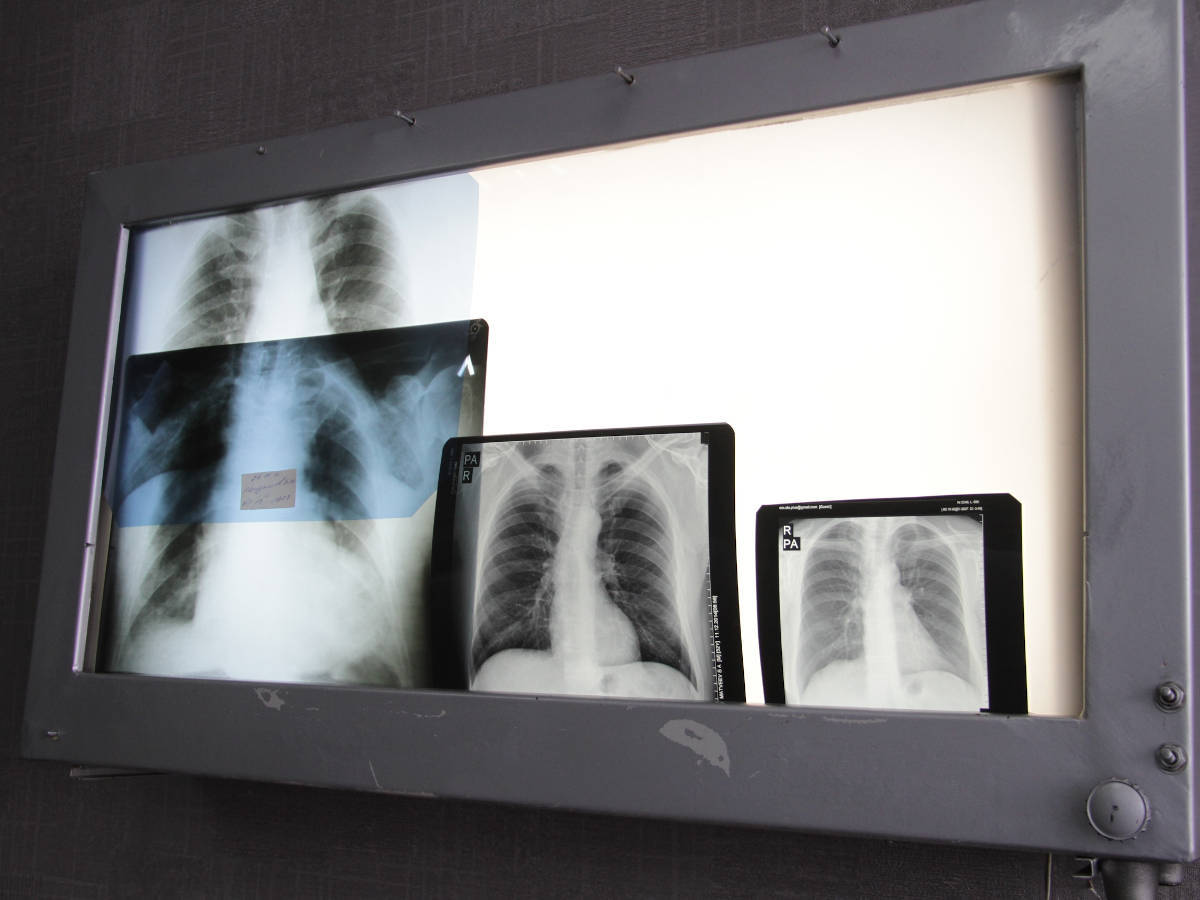

В ВКО в отделении принудительного лечения от туберкулёза больше нет пациентов

Отделение принудительного лечения в селе Акжар, входящее в состав Восточно-Казахстанского областного фтизиопульмонологического центра, продолжает функционировать, однако сейчас больных там нет. Как сообщили в учреждении, последние два пациента завершили курс лечения и были выписаны в начале октября, передает YK-news.kz.

По официальным сведениям, за последние девять лет основные показатели по туберкулезу в Восточно-Казахстанской области сократились более чем вдвое: заболеваемость — на 53 процента, распространенность — на 49,5, смертность — на 67, детская заболеваемость — на 51 процент.